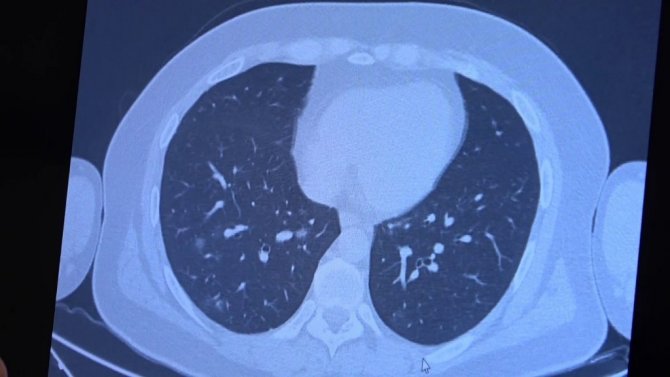

Korona virüs hastalığı genç nüfusta daha fazla görülmeye başlarken Covid-19 aşıları tamamlanan 60 yaş üstü vatandaşlardan bazıları ise korona virüse yakalanmaya devam ediyor. VM Medical Park Samsun Hastanesinde görev yapan Göğüs Hastalıkları Uzmanı Prof. Dr. Şevket Özkaya ise aşının gerçek yaşam sonuçlarını gözler önüne serdi. 2. doz aşıları tamamlanmış fakat Covid-19 servisinde yatan hastaların akciğer tomografilerini inceleyen Prof. Dr. Özkaya, bu kişilerin akciğer tutulumları olduğu halde hastalığı hafif atlattıklarını söyledi.

Bugüne kadar aşının etkilerini hep laboratuvar ortamında antikor üretip üretmemesi ile değerlendirdiklerini belirten Prof. Dr. Özkaya, "Vatandaşlarımız aşılarını olduktan sonra ilk gerçek yaşam sonuçlarını yeni yeni almaya başladık. Gerçekten aşı yaptığımızda antikor oluşturuyor ama bu antikor kişiyi koruyacak mı diye merakla beklediğimiz sorunun cevabını, insanlar 2. doz aşısını olduktan bir ay sonra ortaya çıkmaya başladı. Bu hastalar korona virüsü kaptığında yeni yeni korumaya başladığını anladık. Bir örnek vermem gerekirse, 84 yaşında bir hastamız 2. doz aşısını olduktan sonra eşiyle beraber Covid-19 oluyor. Korona virüsü akciğer tutulumları olduğu halde çok hafif şekilde atlattılar. 65 yaşında başka bir hastamızı göstermek gerekirse, bu hastamız da 2. doz aşısını olmuş ve aradan 1 ay geçtikten sonra antikor da oluşmuş. Bu antikor bu kişiyi koruyacak mı diye gerçek yaşam sonuçlarına baktığımızda, koronanın hastanın akciğerlerine indiği halde çok hafif atlattığını görüyoruz. Eğer bu kişi aşı olmasaydı, hastaneye yatarak daha ağır geçirebilirdi" diye konuştu.